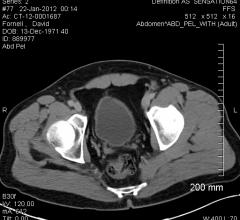

The biggest trend in contrast media injector technology today is one seen throughout all of healthcare — doing more with less, or maximizing the utility of existing technology. In the case of contrast media, vendors are focusing on systems that make full use of the existing contrast supply in an effort to reduce contrast dose. This shift is happening with contrast media across multiple modalities. Vendors are also allowing injector systems to integrate with electronic medical records (EMR), picture archiving and communication systems (PACS) and other technology to automatically record and analyze contrast dose data.